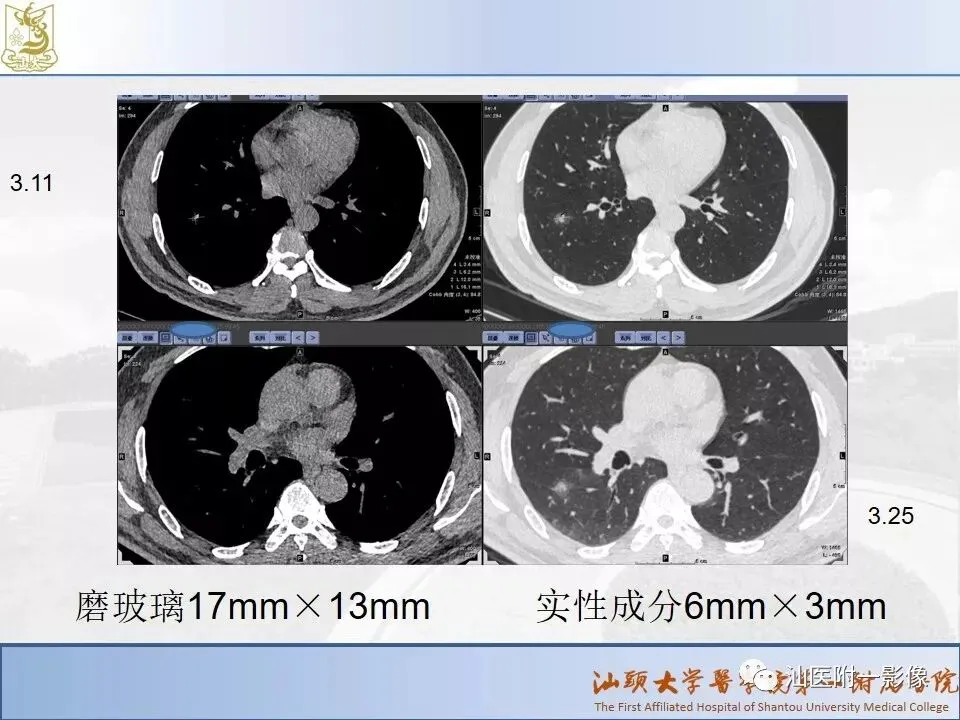

肺结节分类、处理及浅识肺结节分类影像报告和数据系统(Lung-RADS)

来源:汕医附一影像

说明:本课程病例主要来源于本院病例及参考资料,

无涉及病人隐私,仅做教学用途。